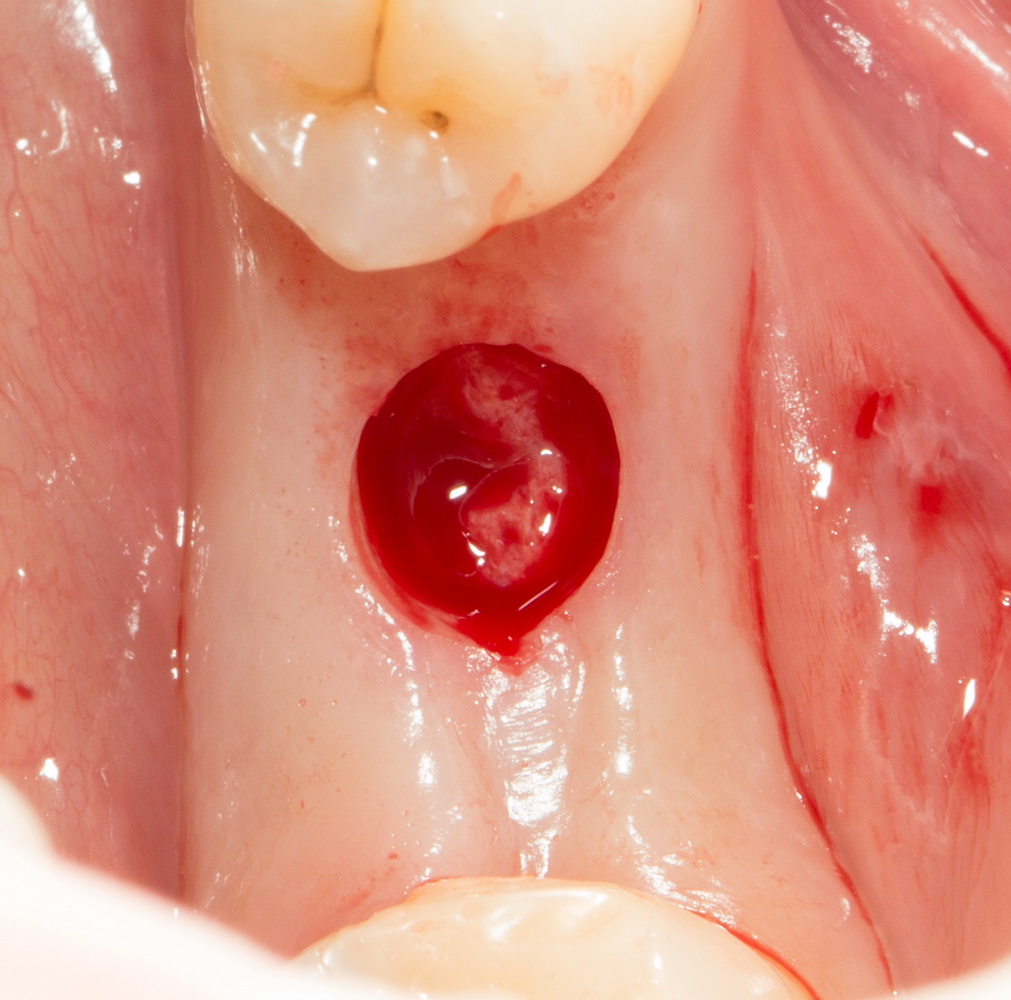

Рекомендации по установке имплантов. Для всех. Часть II.